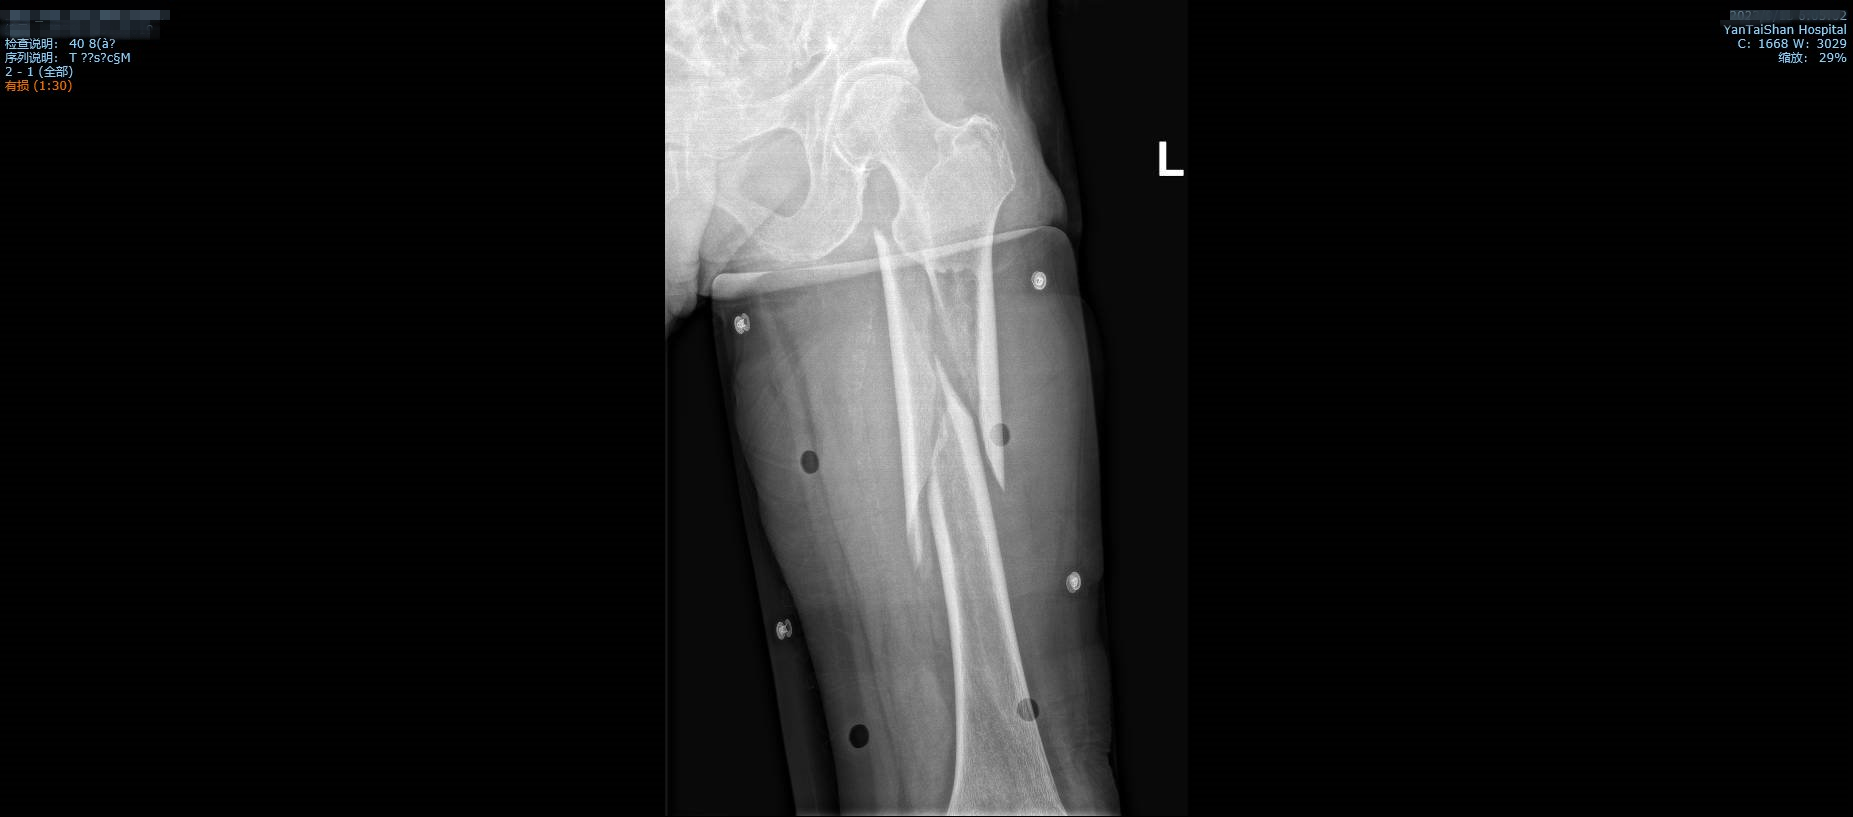

术前影像学检查。

前几天,91岁的王奶奶在家不慎跌倒,家人连忙将她送到了烟台山医院南院骨科,拍片检查后发现:股骨干骨折。家人对此十分担心,不知道王奶奶能否渡过这一关。

入院后,南院骨科孙冰主任对其进行仔细检查,发现王奶奶的骨折类型是“32c复杂股骨骨折”,这种多节段、不规则的骨折可导致大范围出血,严重者出血量高达2000ml,容易出现出血性休克,危及生命。并且王奶奶多系统功能均有障碍,她有着20多年的糖尿病史,患高血压15年,贫血、肺部感染、胃肠功能紊乱合并各类并发症……血红蛋白甚至只有59.00g/L。